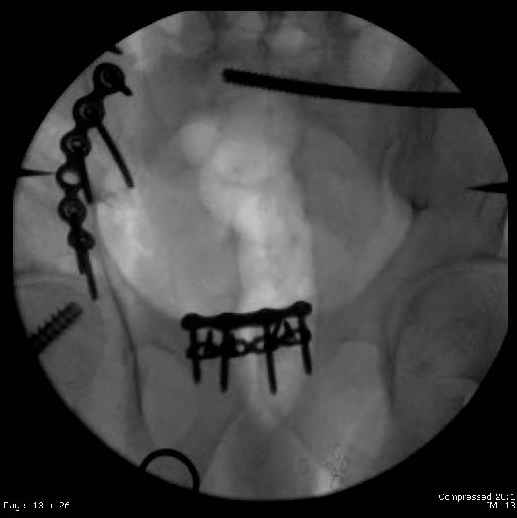

Here are the postop fluoros.

First exposed symphysis & clamped w/Faraboeuf as close to anatomic as possible.

Then extended to R ilioinguinal,really just the lateral window.

Reduced the triangular wedge piece of iliac wing to posterior intact ilium (crescent), held w/k-wire, then used 3-hole push plate to keep from moving, lagged from lat-med w 3.5 screw.

Then 6-hole plate along brim with 1 screw in R sacral ala. Then lagged 2 screws along crest A --> P. finally 10-hole plate along inner aspect of crest. R posterior ilium still a bit stepped off.

Symphysis then 'fine-tuned' & reduced as close as possible to anatomic (but, still with forward rotation of R hemipelvis - or, is it extension?) Accepted that amount of deformity and plated symph

with 4-hole symphyseal plate.

Fluoroed L SI joint and it seemed stable, but wide. So, applied c-clamp to try to squeeze down L SI joint (and note, on the last slide attached, that it's still wide), and got it closer. Single perc Iliosacral screw 40mm thread.

Applied second plate anteriorly on symphysis as I wasn't confident L SI was as stable as it could be and wanted to protect it better.